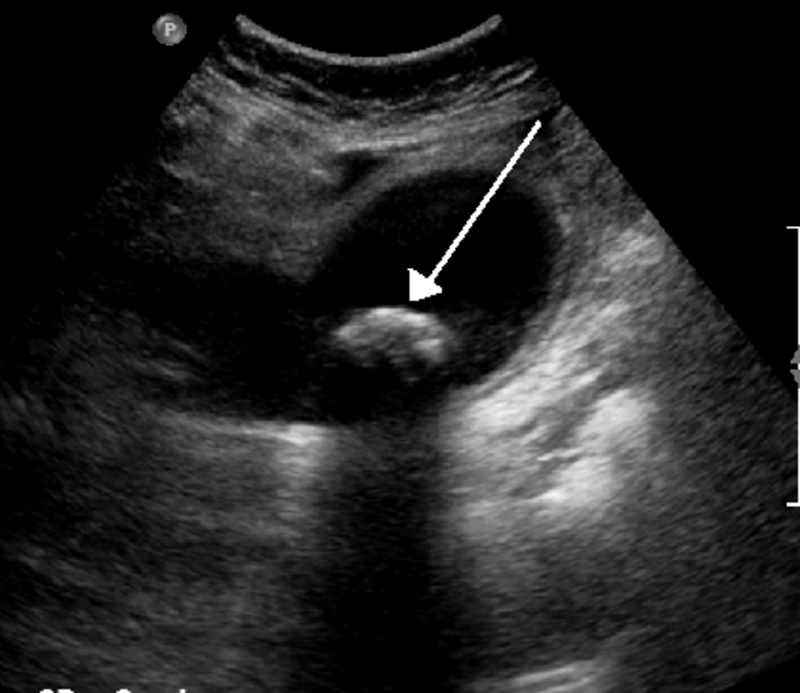

Le famigerate coliche biliari, tanto dolorose, inducono la persona a recarsi al PS dove l'esame ecografico può mostrare la presenza di calcoli biliari, sabbia biliare o anche nulla. Se c'è una colecistite in atto, le pareti della colecisti possono apparire ispessite con o senza liquido pericolecistico. L'ecografia può mostrare anche una dilatazione, più o meno significativa, delle vie biliari intra ed extraepatiche, il che può far sospettare che vi sia la presenza di calcoli nella parte terminale delle vie biliari (papilla di Vater).

Calcoli multipli in presenza di colecistite